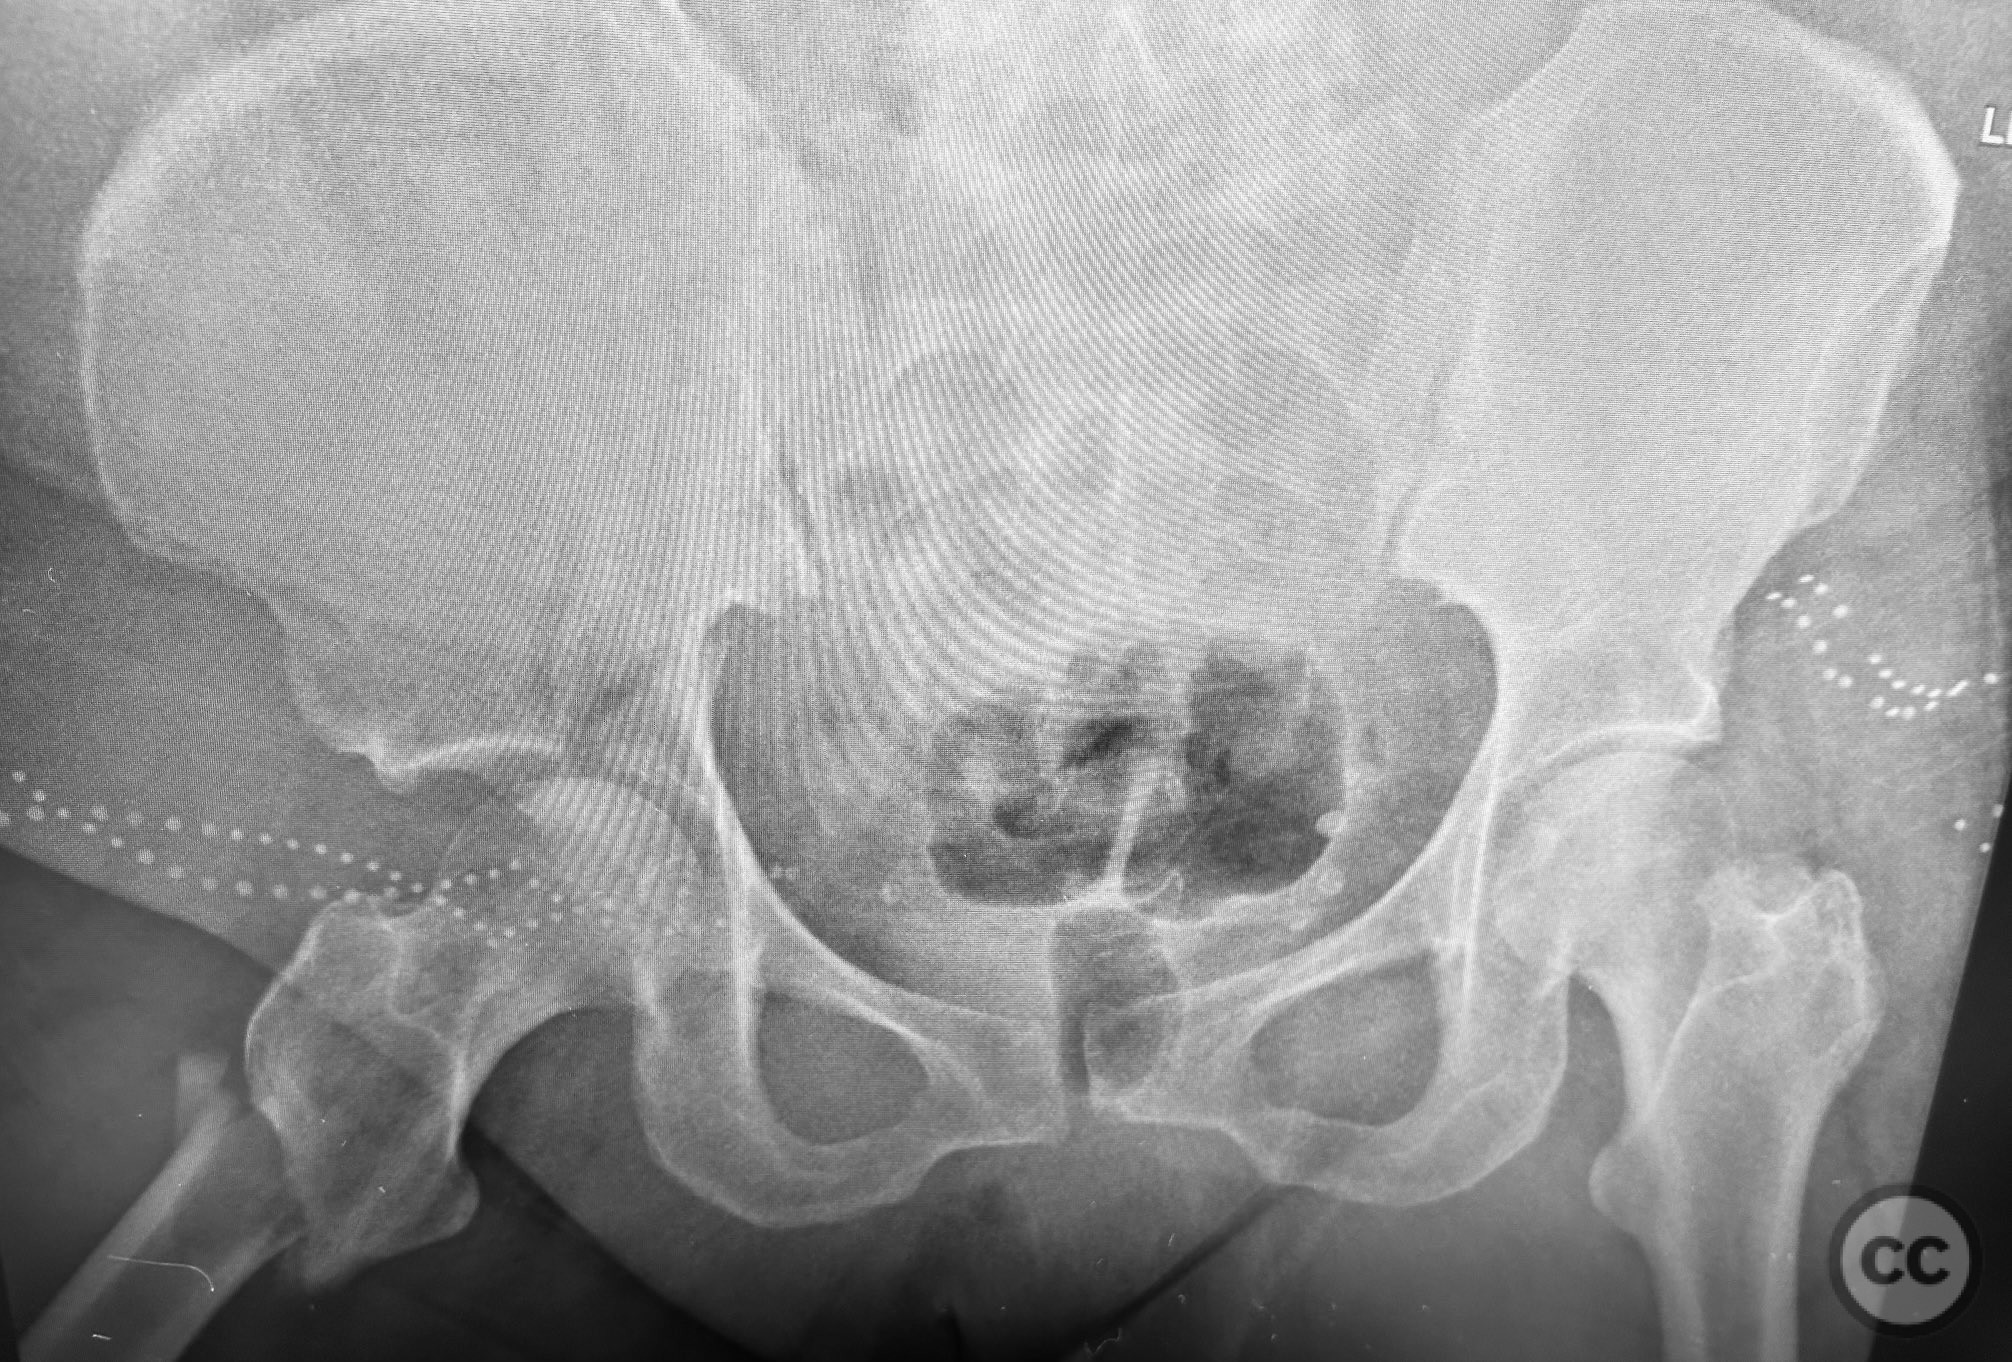

Clinical and radiological findings:  An active but obese senior patient presented with a complex acetabular fracture following a lap belt injury. The patient had significant anterior abdominal surgical scarring from prior gynecological operations. Initial clinical assessment revealed a closed injury with associated soft tissue trauma in the inguinal and lower abdominal regions. Radiographs and computed tomography demonstrated an AO/OTA 62C1 (AsBothCol) pattern, with both anterior and posterior column involvement and displacement. There was no evidence of neurovascular compromise. Notably, the lap belt injury zone showed extensive soft tissue contusion and devitalization.